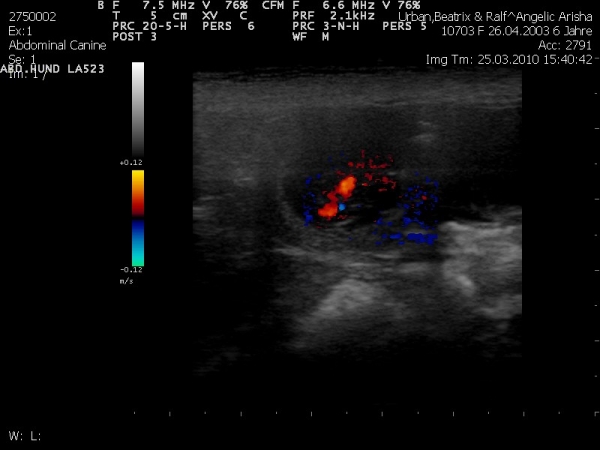

wollte euch mal mitteilen das unsere Arisha Trächtig ist und wollte euch mal ein paar Ultraschallbilder zeigen.

Vom wievielten Tag ist das Bild?

die Bilder sind vom 25 Tag.

Kann man auf den Bildern denn schon erkennen, wieviel Baby´s da sind ??